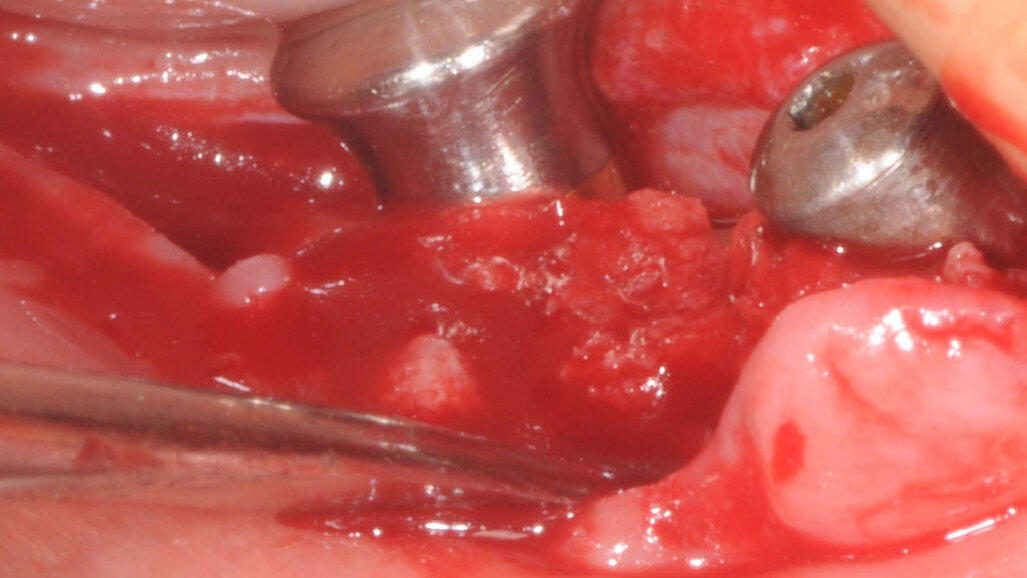

La terapia anticoagulante non è stata interrotta prima della chirurgia ed è stata somministrata la profilassi antibiotica come da protocollo. È stata eseguita un’incisione crestale senza tagli di scarico che è stata estese distalmente fino al trigono retromolare per esporre la branca mandibolare ed avere un sito per raccogliere osso autologo con una fresa carotatrice. Sono state eseguite le osteotomie a basso numero di giri come da protocollo BTI per ottenere un’ulteriore quantità di osso autologo raccolto dalle frese e inseriti due impianti BTI Core 3,75 x 4,5 e 3,5 x 6,5 rispettivamente in posizione 46 e 45.

L’osso autologo è stato mescolato con gel piastrino ottenuto da centrifugazione del sangue del paziente mediante metodica Endoret BTI. La membrana ottenuta è stata applicata a protezione della corticale vestibolare. Ulteriori membrane di gel piastrino sono state applicate sopra l’osso autologo. La stabilita primaria di entrambi gli impianti era superiore ai 50 Newton per cui sono stati avvitati i pilastri Multi-Im e i pilastri di guarigione per un tecnica con una sola chirurgia. Sono state applicate suture sintetiche non riassorbibili a punti staccati (Figg. 3–10). Successivamente è stata eseguita una Rx di controllo. Le suture sono state rimosse a due settimane e la paziente riferì di avere avuto disagi minimi, senza ematomi o edemi estesi e scarsa dolenzia che non richiese l’assunzione di antinfiammatori.